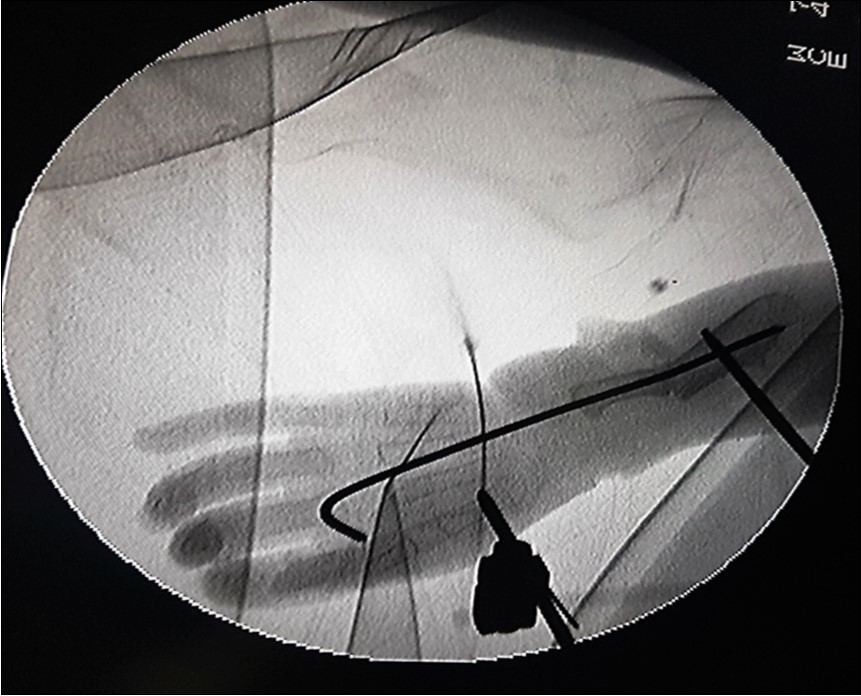

The ulnar osteotomy was stabilised with an intramedullary 2.0mm Kirchner wire (K-wire). Wrist bridging external fixators were mounted bilaterally to maintain correction until 12 weeks after surgery. Intraoperative fluoroscopic image of the correction of the left forearm is depicted in figure 3.

Figure 3.Fluoroscopic image showing the K-wire running from the 3rd metacarpal to bridge the ulnar osteotomy. The Schanze screws of the external fixator are shown, one each in the first metacarpal and in the proximal ulna with the forearm in pronation.